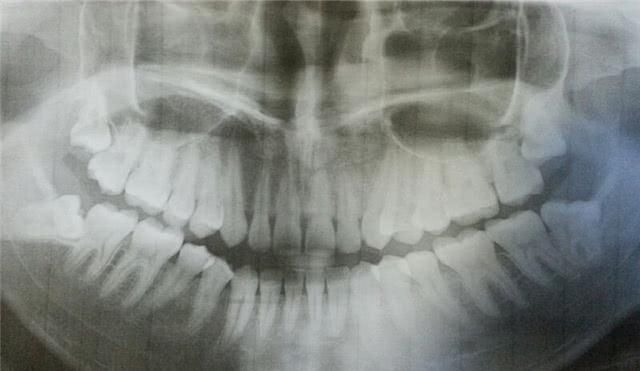

智齿是人成年后才开始进行生长的,是人一生中最后长出的牙齿,并且所生长的地方也是口腔的最深处,这样就会让我们每天的清洗工作变的特别的困难,刷牙的时候往往不能很好地刷到智齿这一块,大家肯定都有过出现紧急情况导致一天或者两天没有刷牙的情况出现的,打个哈欠的时候肯定也感受过味道。这就是为什么拔出来的智齿会这么臭的原因之一!

【 智齿|为什么拔出来的智齿会这么臭?听完医生的解释,觉得“难为情”】清洗的不方便就会带来有些残留物不能够清洗掉,我们咀嚼食物的时候都会将食物咬得很碎,所以留在牙齿之间的残留物也会比较不易于清理,在加上我们的咀嚼习惯一般都是用的后槽牙,很少会用到门牙部位的牙齿去咀嚼食物,所以东西堆积多了也就是为什么拔出来的智齿会这么臭呢!

我现在每天吃的东西也是千变万化,比起以前来说肯定有着很多的变化,各种甜品,水果,油炸等等都会有残留物留在我们的口腔内,并且根据我们咀嚼东西的习惯也都将这些残渣都大量的集中在了智齿这块区域,这样的长期的积累不用多说,大家通过自己的想象肯定也能够只有会产生什么样的后果,为什么拔出来的智齿会这么臭大体上就是因为这些残渣所造成的。

智齿的发炎也是因为这些引起的,疼到大家可能生活都不能自理的时候就会到口腔医院去进行拔出了,有些没有严重到需要拔牙的也会有很多医生说平时需要多注意清理的问题,让大家刷牙都估计到上下的后槽牙,同时也会让大家多漱口来保持口腔的清洁。智齿如果不好好管理真的会让人痛不欲生的,出现过问题或者还没有出现问题的朋友也需要多按照医生说的口腔清理去做呢!